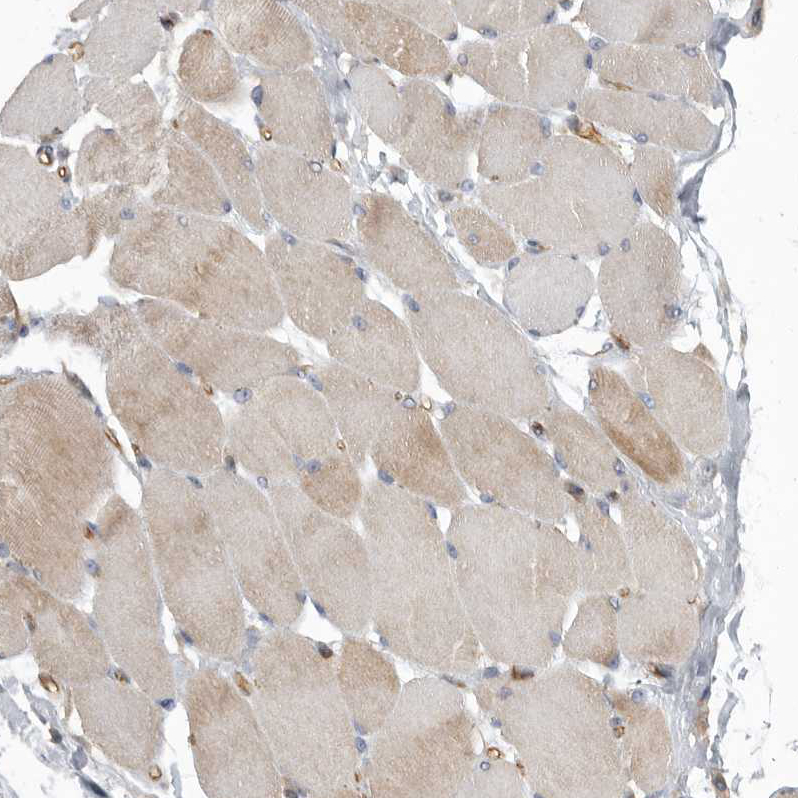

Immunohistochemical staining of human heart muscle shows strong cytoplasmic positivity in myocytes.